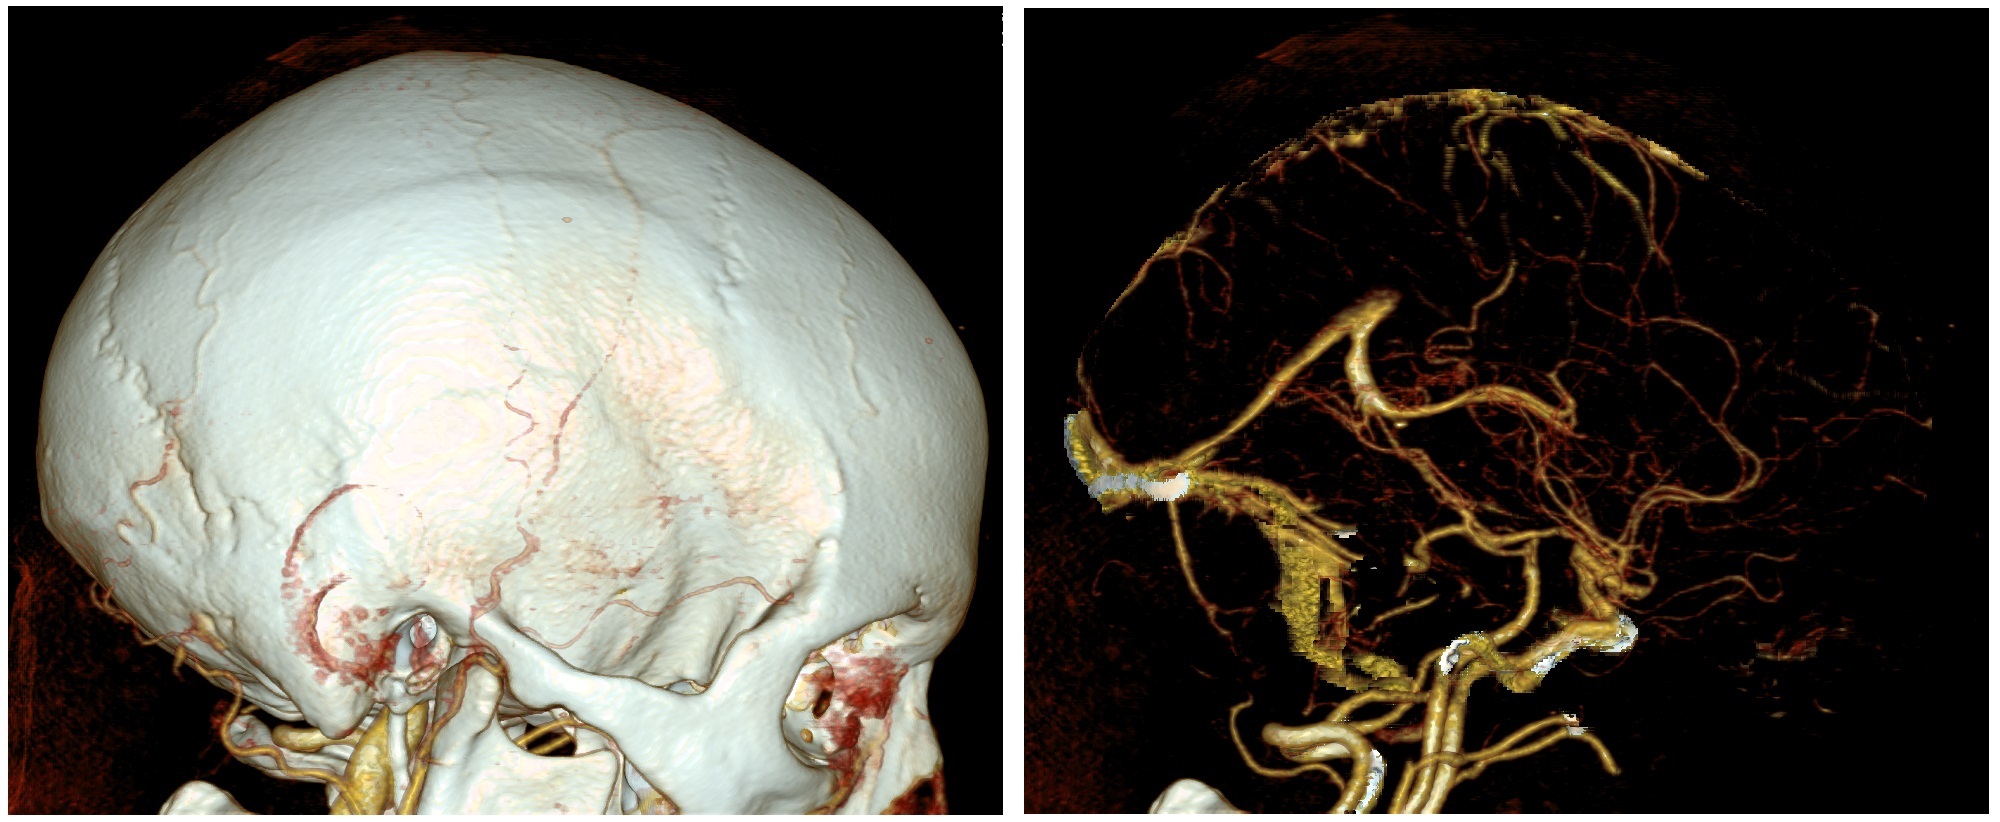

볼륨 렌더링은 얇은 단면 단층 촬영 프레젠테이션이나 최대 강도 투영을 포함한 3D 모델의 투영과는 구별된다.[1] 하지만 기술적으로 모든 볼륨 렌더링은 2차원 디스플레이에 표시될 때 투영이 되므로, 이 둘의 구분이 다소 모호하다. 그럼에도 불구하고 볼륨 렌더링 모델은 현실적이거나 관찰 가능한 표현을 만들기 위해 색상[2]과 음영[3]을 혼합하여 특징을 나타낸다.

볼륨 렌더링은 얇은 단면 단층 촬영 프레젠테이션과 구별되며, 최대 강도 투영을 포함한 3D 모델의 투영과도 일반적으로 구별된다.[1] 하지만 기술적으로 모든 볼륨 렌더링은 2차원 디스플레이에서 볼 때 투영이 되므로, 투영과 볼륨 렌더링의 구분이 다소 모호하다. 그럼에도 불구하고 볼륨 렌더링 모델의 전형적인 예는 현실적이거나 관찰 가능한 표현을 만들기 위해, 예를 들어 색상[2]과 음영[3]을 혼합하여 특징을 나타낸다.